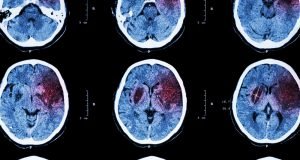

Bei einem Schlaganfall handelt es sich um eine örtliche Störung innerhalb des Gehirns. Diese wird in der Regel durch eine…

Typische Symptome für den Schlaganfall sind Lähmungen oder auch Hörstörungen bis zur Taubheit. Die Lähmungen treten an Arm und Bein…